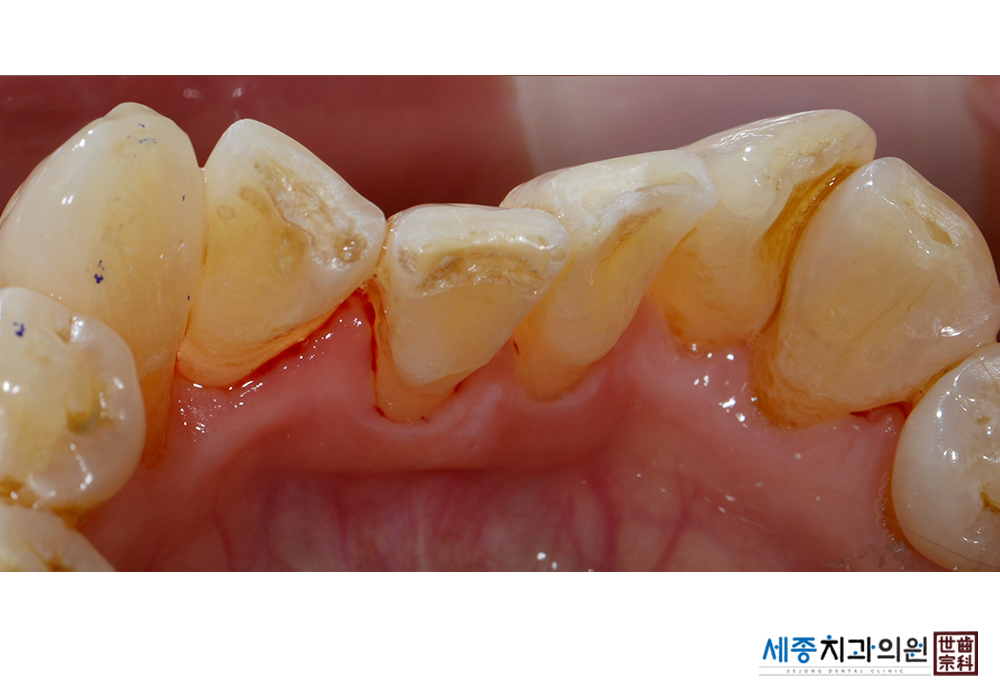

[스케일링] 치주질환 예방 스케일링

치료전 : 2019-09-24

가글마취&저주파 스켈러를 사용한 스케일링